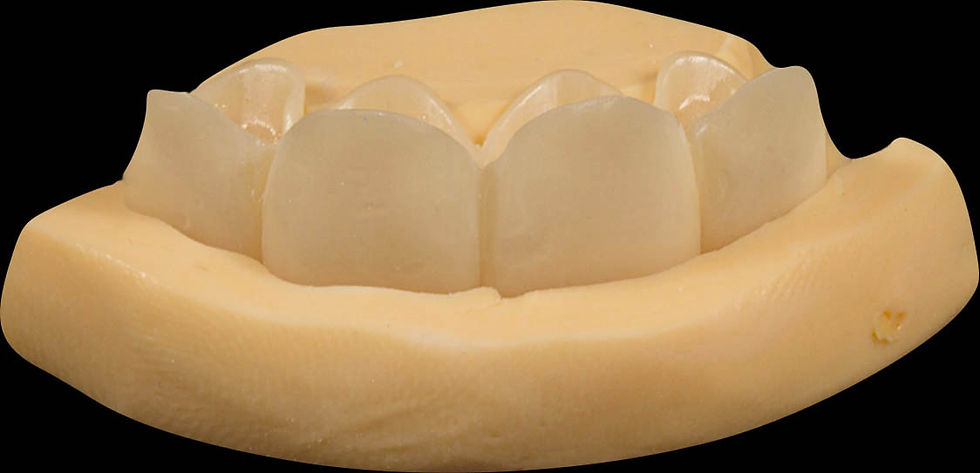

Before the creation of the zirconia final structure, we verify the correct passivation through a biomedical resin model

Model and temporary prosthesis positioned onto the silicone rim.